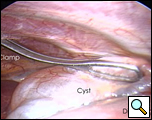

In the operating room, under general anesthesia and one lung ventilation, the thoracoscope was introduced at the right midaxillary line and the 7th intercostal space (Video 1 below). The cyst was readily visualized at the anterolateral aspect of the right pericardium, measuring approximately 9x6cm (Figure 3). The phrenic nerve was seen posterior to the cyst. The second incision was made at the anterior axillary line in the 4th intercostal space. A ring clamp was used to grasp the cyst (Figure 4). The third incision was made at the scapula line in the 5th intercostal space. Thoracoscopic scissors and cautery (at a low setting to minimize the chance of cardiac arrhythmias) were used through that port to dissect the cyst from the pericardium (Figure 5). The connection between the cyst and the pericardial space was identified. It was small, and was divided with the scissors. The dissection of the posterior aspect of the cyst completed the removal. The phrenic nerve was clearly visualized at all times. The pathology report confirmed the diagnosis of a benign mesothelial-lined cyst (Figure 6).

| Figure 3.: Intraoperative view of pericardial cyst. | Figure 4. Ring clamp retraction of pericardial cyst. |